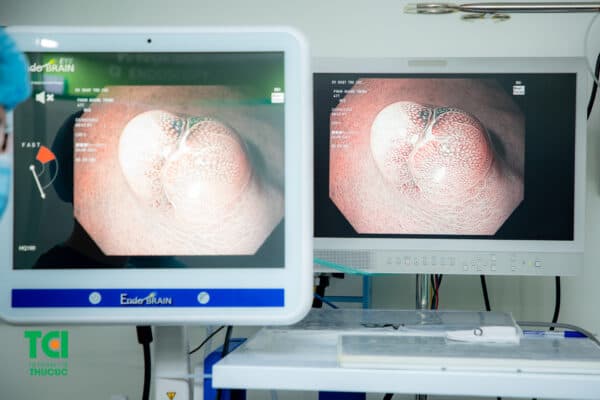

Nội soi đại tràng là phương pháp chẩn đoán hình ảnh tiêu chuyển giúp phát hiện mọi bất thường cũng như bệnh lý đường tiêu hóa. Ống nội soi mềm quan sát kỹ càng bên trong thành đại trực tràng, trong trường hợp có polyp, bác sĩ có thể trực tiếp cắt bỏ ngay trong quá trình nội soi khi có chỉ định.

Nội soi đại trực tràng giúp phát hiện mọi bất thường và bệnh lý ở đường tiêu hóa dưới.